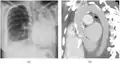

Extensive left-sided fibrothorax

Chest radiograph displaying inhomogeneous opacification of the left half of the chest that is fibrothorax

Autopsy specimen showing extensive pleural fibrosis